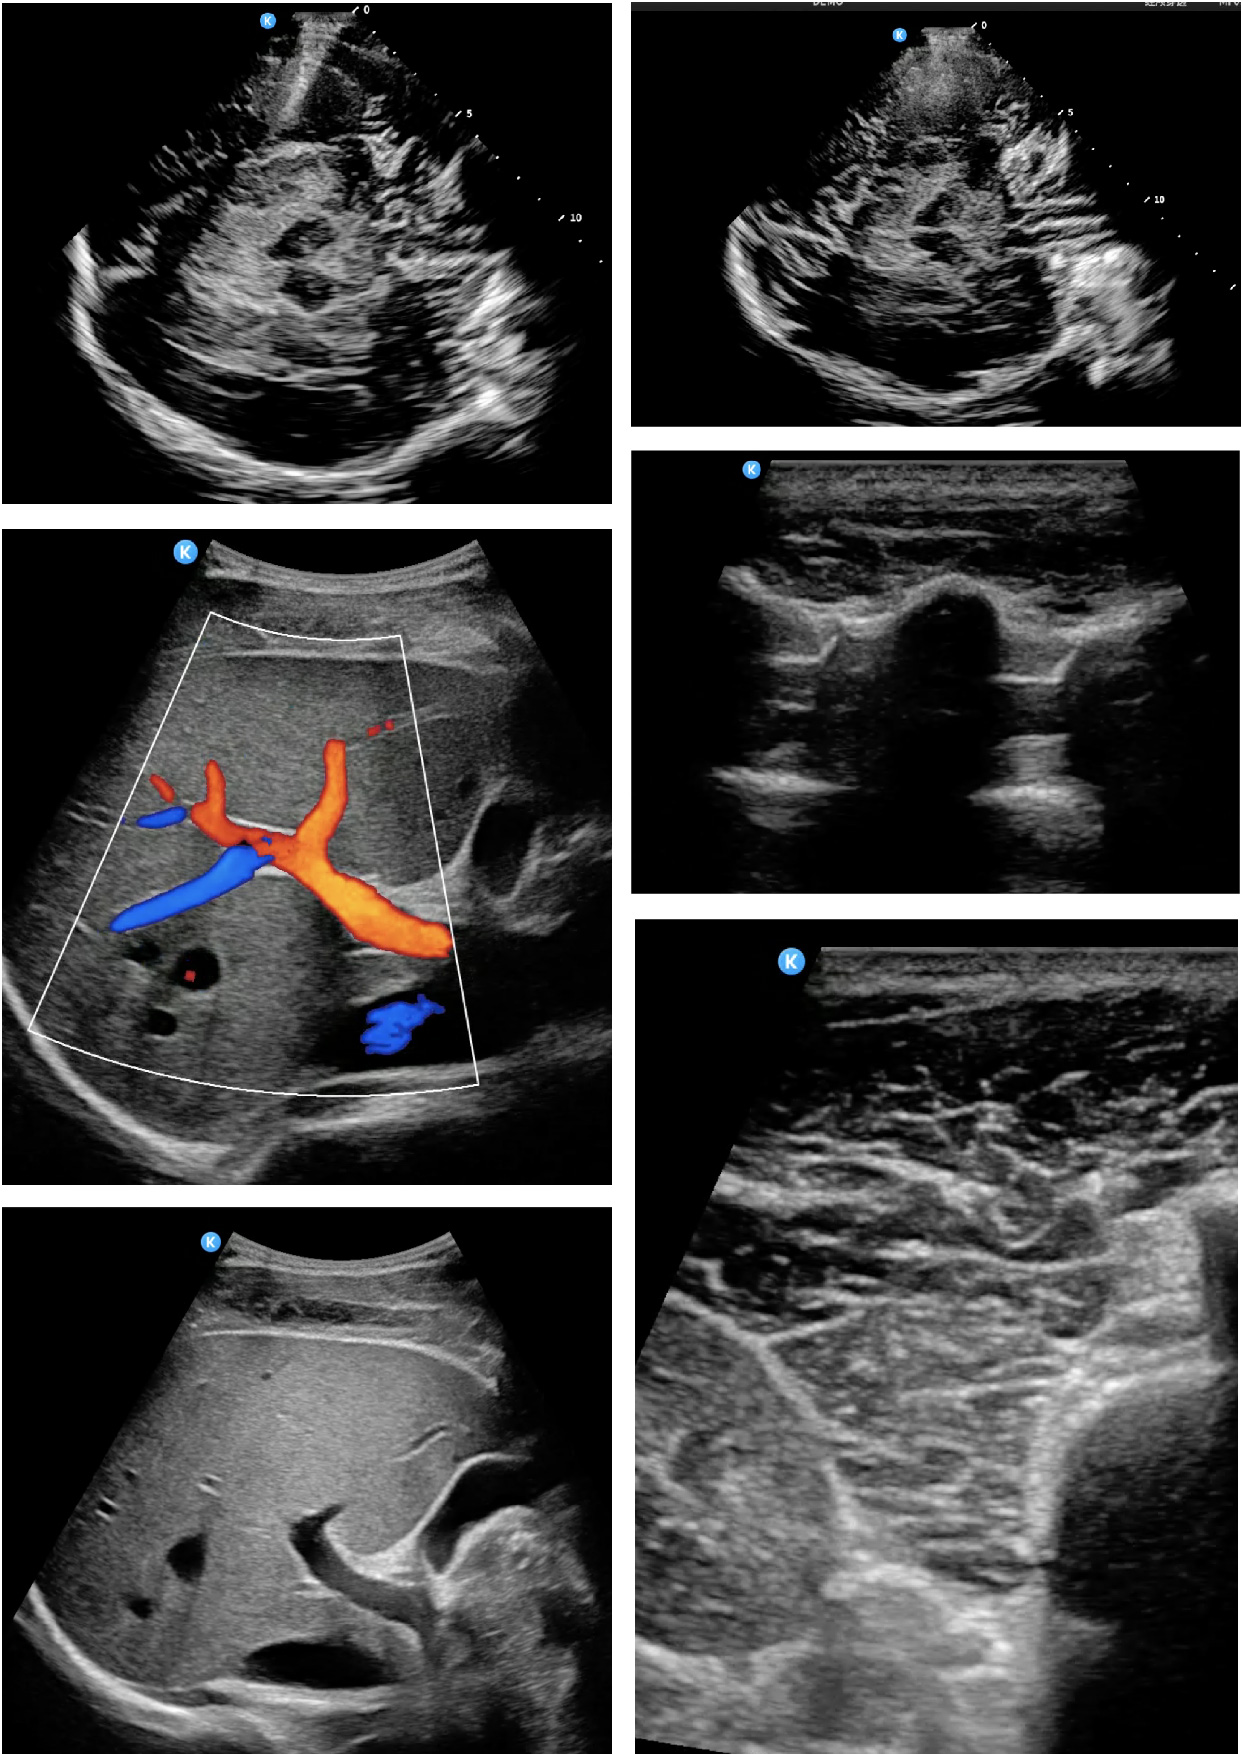

在这场聚焦技术跃迁的大会上,鲲为科技展示的“低频高分”经颅超声成像技术以创新性低频设计融合高分辨率成像能力,显著提升了超声波对致密颅骨的穿透效果,一举突破传统经颅超声成像的瓶颈,为脑部疾病的无创精准探查开辟全新视野。

这一技术突破在临床诊疗层面意义非凡。清晰、稳定的颅内结构及血流成像,使医生能在床旁即时评估急性脑血管病变(如脑卒中)、实时监测颅内压变化、对神经重症和围手术期病人进行监测,极大缩短了诊疗决策时间,为神经危重症患者争取宝贵的救治机会。在神经退行性疾病与儿童诊疗领域: 为帕金森病的早期诊断与鉴别提供了重要的影像学依据(如中脑黑质致密带的高回声评估);可对儿童颅脑结构(如发育异常、出血等)及脊柱(如脊髓圆锥位置、脊柱裂筛查)进行评估,“低频高分”经颅成像技术在脑疾病检查中展现出独特价值。

技术展示区热度爆棚,众多与会青年医生汇聚鲲为公司展台,争相观摩体验:

“图像穿透力和分辨率令人印象深刻,这让我们在急诊环境下快速评估脑血流灌注成为可能,是真正改变临床实践的工具。”